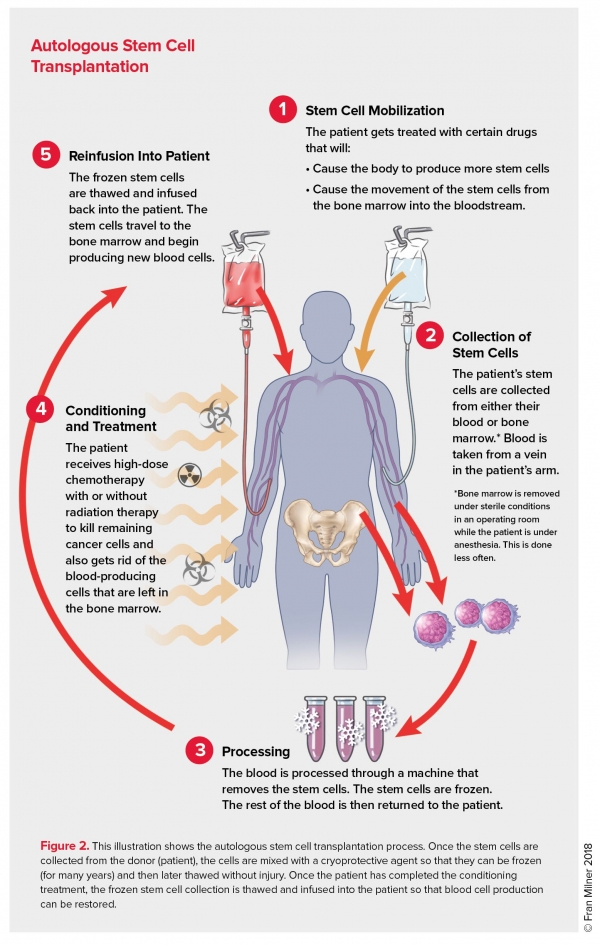

Stem Cell Transplantation, Autologous Stem Cell Transplantation